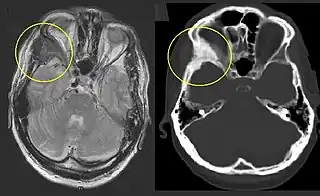

Tomografía y resonancia magnética

Pueda ayudar evaluar con exactitud la magnitud de la afectación ósea. La intensidad de señal en la resonancia magnética es moderadamente baja en T1, mientras en T2 es alta o media. Con gadolinio, la mayoría de las lesiones muestra un incremento central de contraste y algunos anillos periféricos.[5] En general, la intensidad de la señal depende de la cantidad de trabéculas óseas, colágeno, quistes y hemorragias. El clásico aspecto en la tomografía es de «vidrio esmerilado», que corresponde al hueso sano que rodea a la lesión.[5]